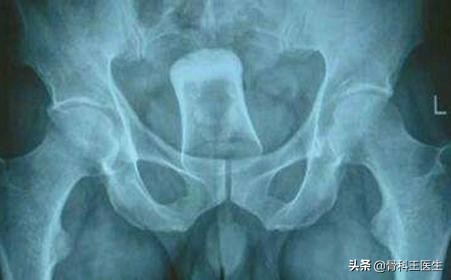

1、肚子切开取异物:

通常是胃镜下取不出的胃里的异物,或者是卡在肠管的异物。